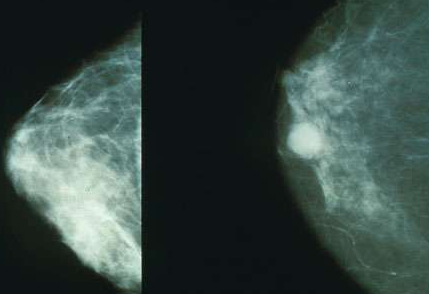

刊登在Appliedand Environmental Microbiology杂志上的一项研究报告中,研究人员发现,有潜力诱发乳腺癌的细菌通常存在于癌症患者的乳腺中;而如果个体健康乳腺中含有大量的有益细菌,这些细菌则会保护女性免于癌症的发生;相关研究或可帮助科学家们利用益生菌来保护女性免于乳腺癌的发生。

文章中,研究者CamillaUrbaniak对经历病灶切除术、良性(13名女性)或癌变(45名女性)乳房切除术的58名患者进行研究,研究人员对患者机体的乳腺组织进行研究分析,同时以23名接受乳房缩小术或增大术的健康女性为对照进行研究;研究者利用DNA测序对组织样本中的细菌进行鉴别,并且培养从而确定所存活的细菌。

研究者发现,当乳腺癌患者机体中大肠杆菌和表皮葡萄球菌的水平增加时,就被认为可以诱导HeLa细胞的DNA发生双链断裂,而双链断裂是最有害的一种DNA损伤,其通常可以被生殖毒素、活性氧自由基及电离辐射诱发产生;DNA双链断裂的修复机制通常非常容易出错,而引发的错误通常会导致癌症发生。

相反,乳杆菌属和链球菌属被认为是促进健康的细菌,而且相比癌变的乳腺组织而言,在健康的乳腺组织这些细菌通常非常普遍,这两种类型的细菌都具有一定的抗癌特性,比如,自然杀伤细胞对于控制肿瘤生长非常重要,而且低水平的免疫细胞往往和乳腺癌的高发生率直接相关,嗜热链球菌就可以产生一种抗氧化剂来中和活性氧自由基,从而降低活性氧自由基对DNA的损伤作用。